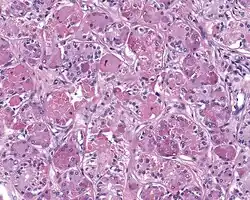

When reviewed by a pathologist, the findings are quite similar to fibrocystic changes of the breast, although they are different enough, that it is now recognized to actually represent a true neoplasm (clonal proliferation) through various studies.[5] Specifically, the lesions are usually well-circumscribed, containing lobules of haphazardly arranged ducts, myoepithelial cells, and acini that have abundant sclerosing or hyalinized fibrosis. Apocrine change is quite common in the ductal cells.[6] The ducts range from small ductules to cystically dilated spaces (more than 4 striated duct-widths across), often containing products of secretion or reactive histiocytes. A very curious and characteristic finding in all of the lesions is the presence of bright pink (eosinophilic) acinar granules (which are altered zymogen).